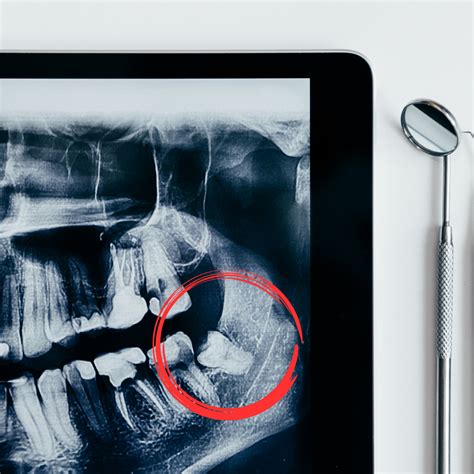

Para determinar el impacto potencial de las muelas del juicio, los ortodoncistas utilizan diversas herramientas diagnósticas, como radiografías y evaluaciones clínicas. Estas evaluaciones permiten a los profesionales anticipar problemas y planificar adecuadamente el tratamiento.

Los ortodoncistas emplean un conjunto de herramientas diagnósticas que les permiten evaluar el impacto potencial de las muelas del juicio y planificar el tratamiento de manera adecuada.

Las radiografías, revelan la posición y el desarrollo de las muelas del juicio, permitiendo identificar si estas se encuentran impactadas, es decir, si no tienen espacio para erupcionar correctamente. Adicionalmente, el ortodoncista analiza la mordida del paciente y el espacio disponible en la boca para determinar si las muelas del juicio podrían generar apiñamiento, desplazamiento o daño en los dientes adyacentes.

De esta manera, los especialistas pueden planificar el tratamiento de manera integral, considerando la extracción de las muelas del juicio, si es necesario, la creación de espacio en la boca o hacer un monitoreo periódico.